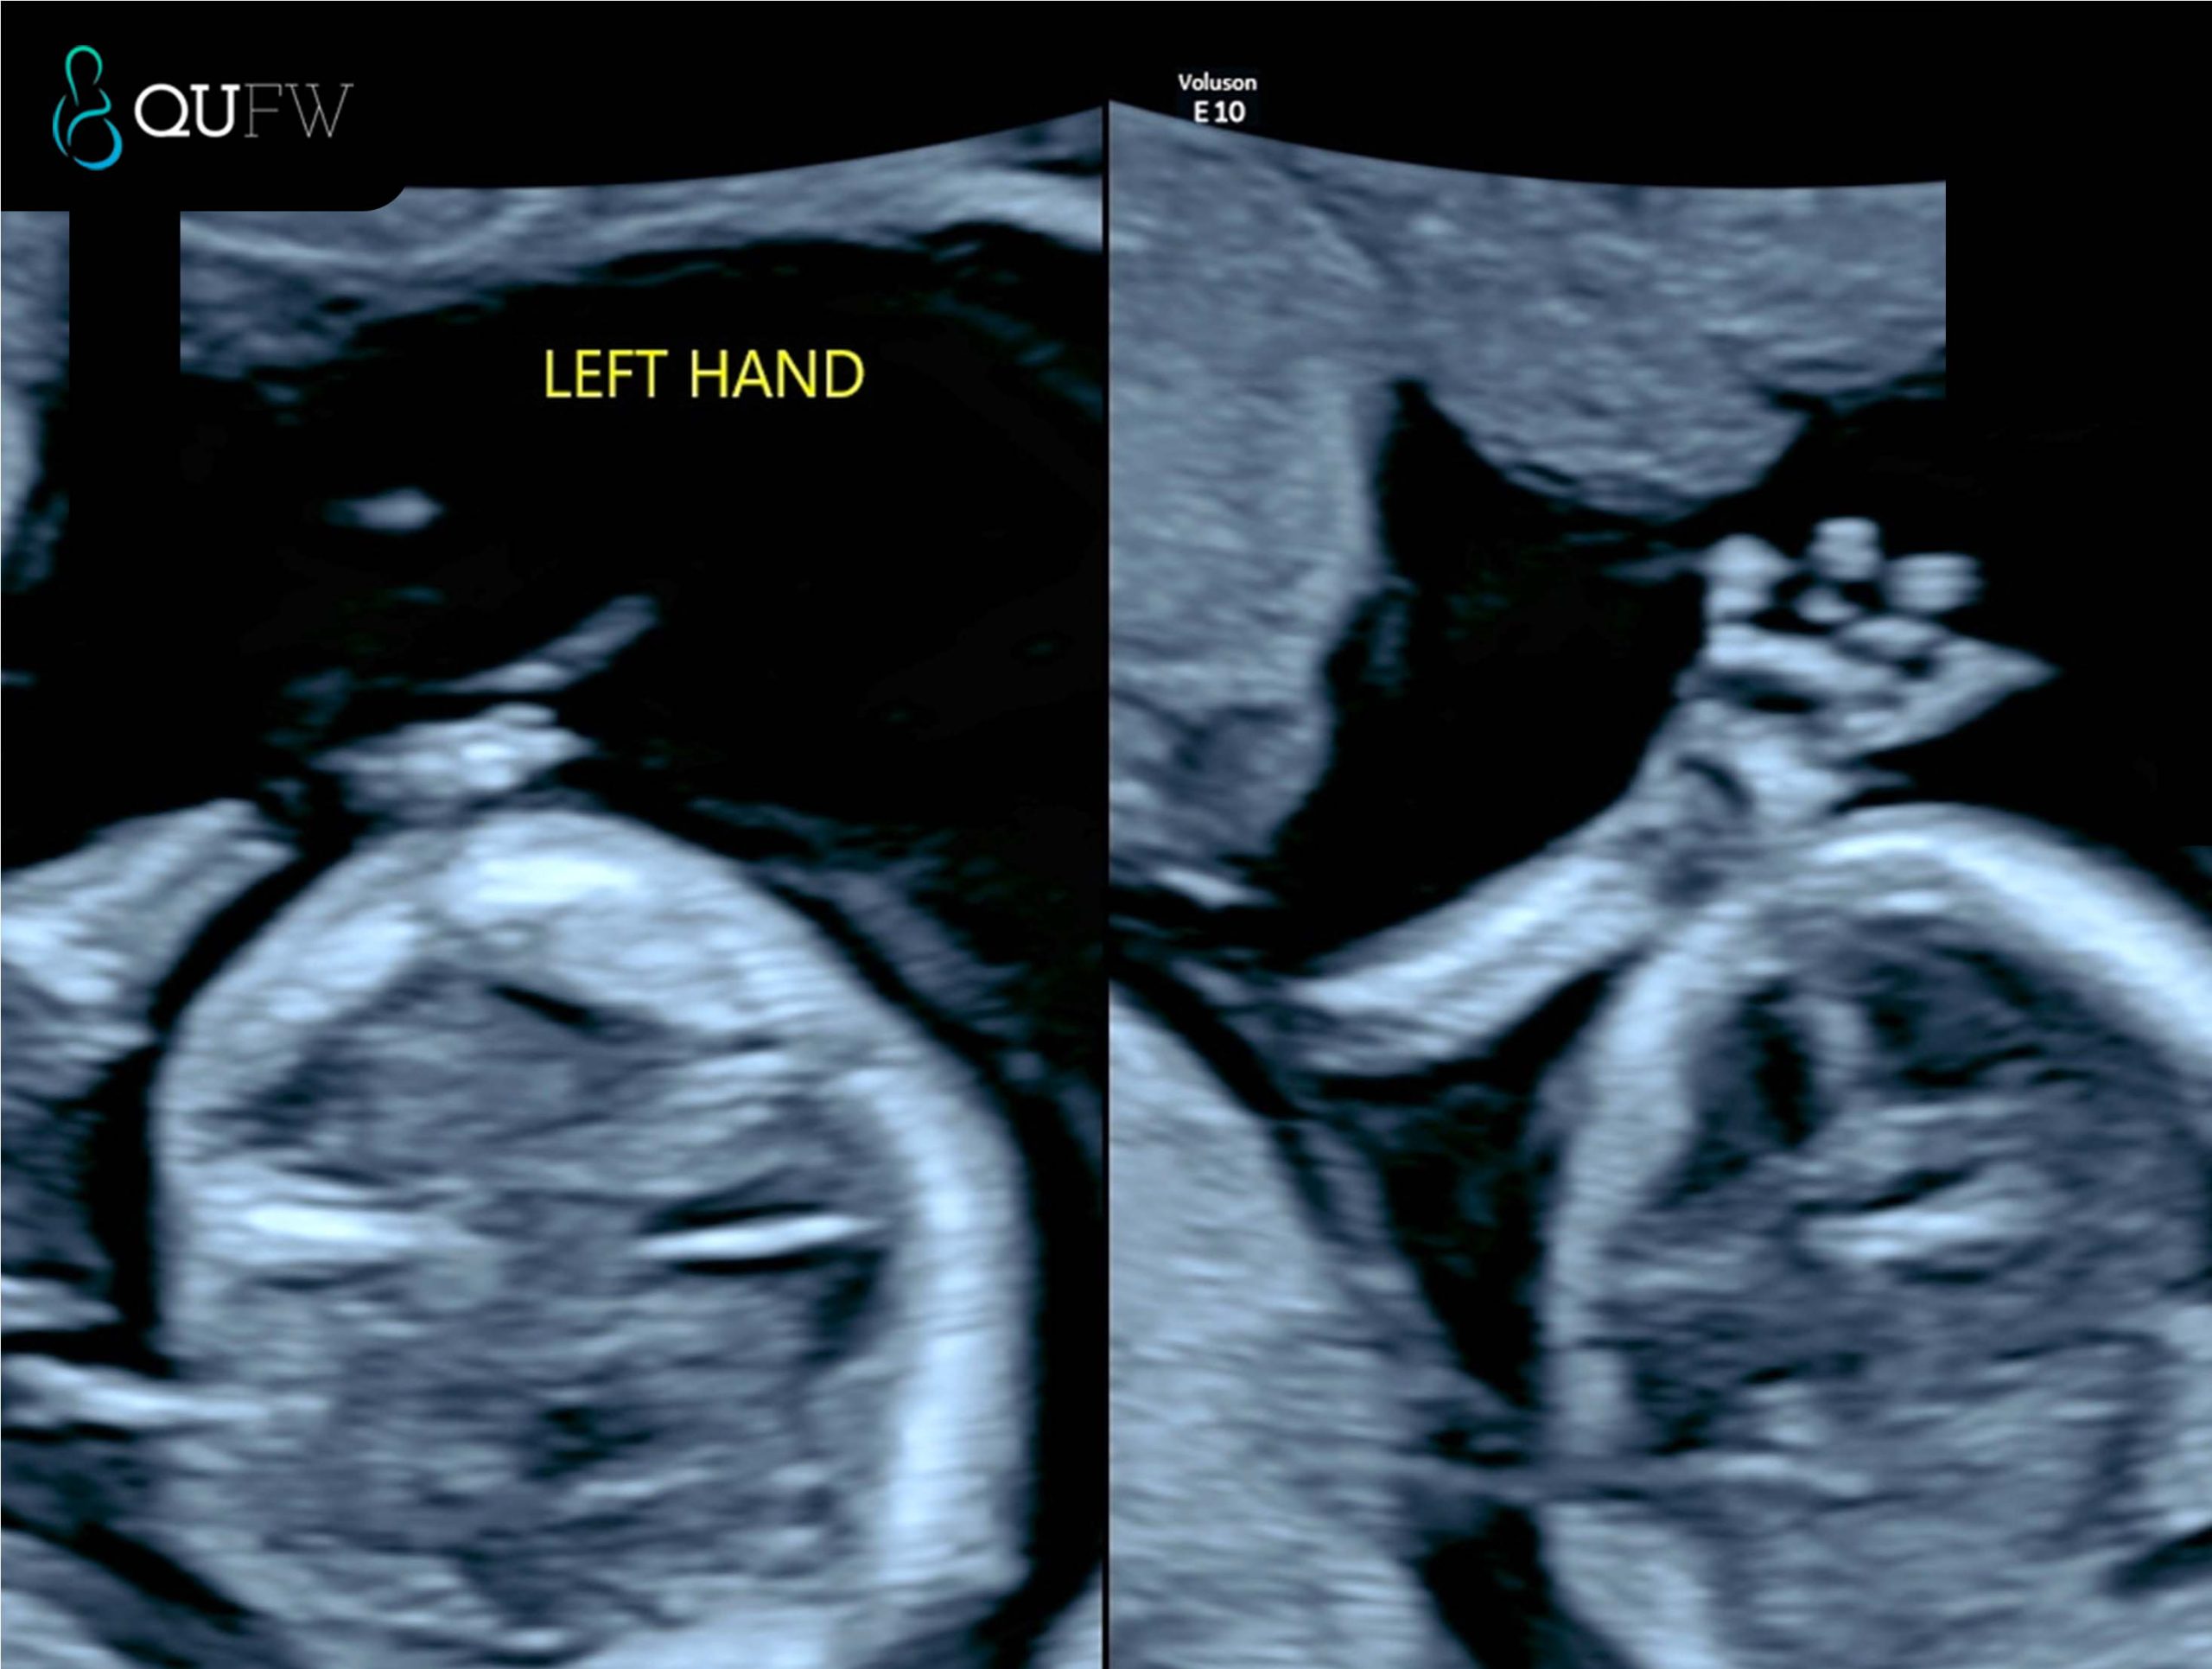

- Extremities – upper limbs/lower limbs including hands and feet

Early structural assessment of the upper limbs